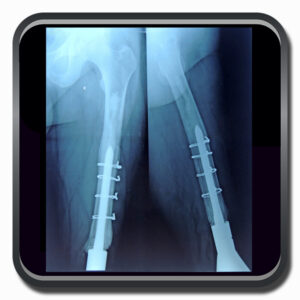

Algumas Cirurgias Complexas realizadas por profissionais da COFIB: